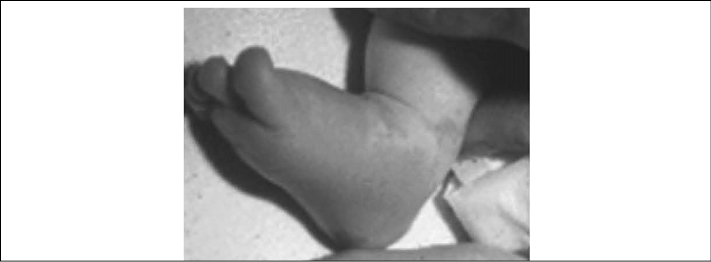

- Peripheral extremity changes, including reddening and/or edema of the palms or soles (see Figure 5), followed by desquamation of the finger and toe tips or transverse grooves across the fingernails (Beau's lines). This is seen in 50-85% of patients,29 and the desquamation usually occurs later in the illness course.

Figure 5. Peripheral Extremity Changes Including Reddening and/or Edema of the Palms or Soles